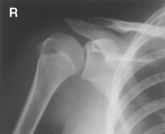

AP external and internal rotation (R)

AP external and internal rotation critique